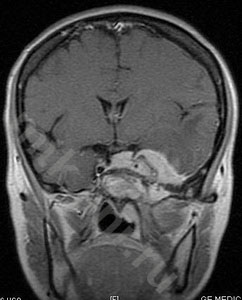

Пример лечения

План конформной протонной лучевой терапии большой (132.5 см3) менингиомы средней черепной ямки (слева), МРТ с контрастом до лечения в середине и МРТ через 12 мес после лечения (справа) – заметное уменьшение опухоли.